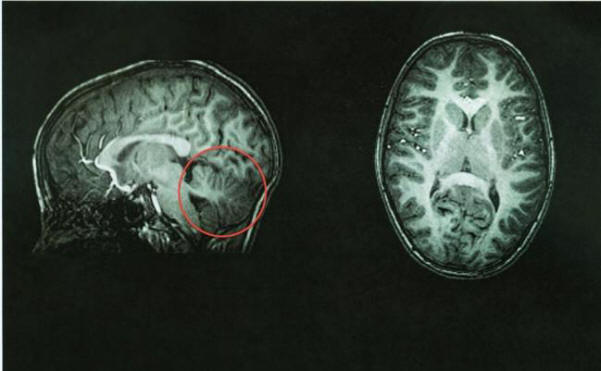

Нормална мозъчна томография, мозъчен мозък в червено

След томография лекарите веднага идентифицират източника на проблема – неговия малкия мозък отсъстваше. Пространството, където трябва да е празно. това мозъчната област се напълни с цереброспинална течност, осигурява защита срещу болестта. Мозъкът отнема около 10 процента от общ обем на мозъка, но съдържа 50 процента от невроните.

Образ на мозъка на китайка без мозъчен мозък